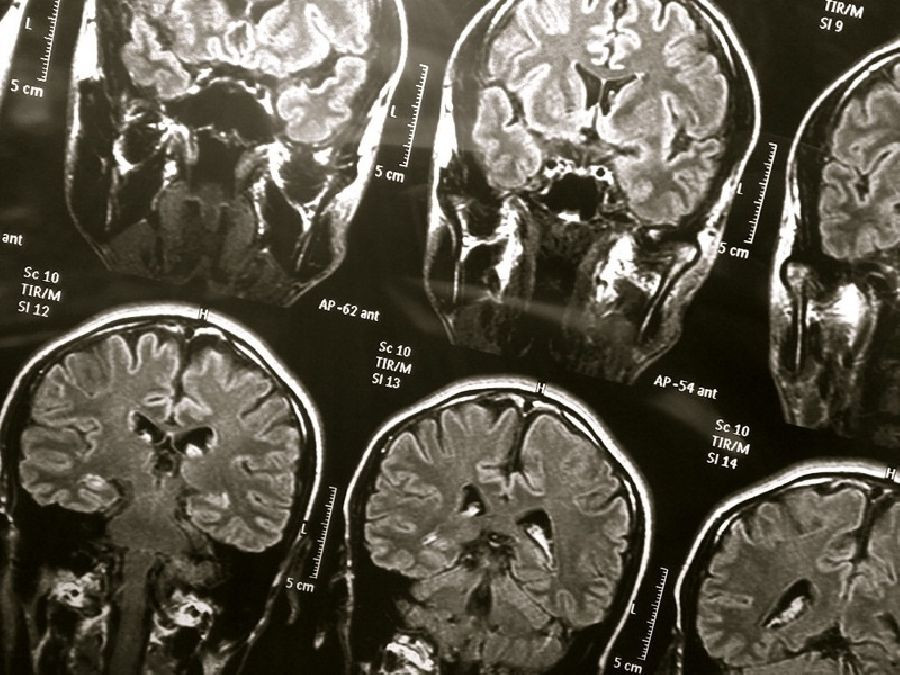

Las personas con espacios agrandados llenos de líquido en el cerebro alrededor de los vasos sanguíneos pequeños pueden tener más probabilidades de desarrollar problemas cognitivos y demencia con el tiempo, según un nuevo estudio publicado en la edición en línea de `Neurology`, la revista médica de la Academia Americana de Neurología.

En el estudio participaron 414 personas con una edad promedio de 80 años, que realizaron pruebas cognitivas de las habilidades de pensamiento y memoria y se les evaluó la presencia de demencia al comienzo del estudio y cada dos años durante ocho años. Se sometieron a escáneres cerebrales de resonancia magnética para verificar espacios perivasculares agrandados en dos áreas clave del cerebro al comienzo del estudio y luego cada dos años durante ocho años.